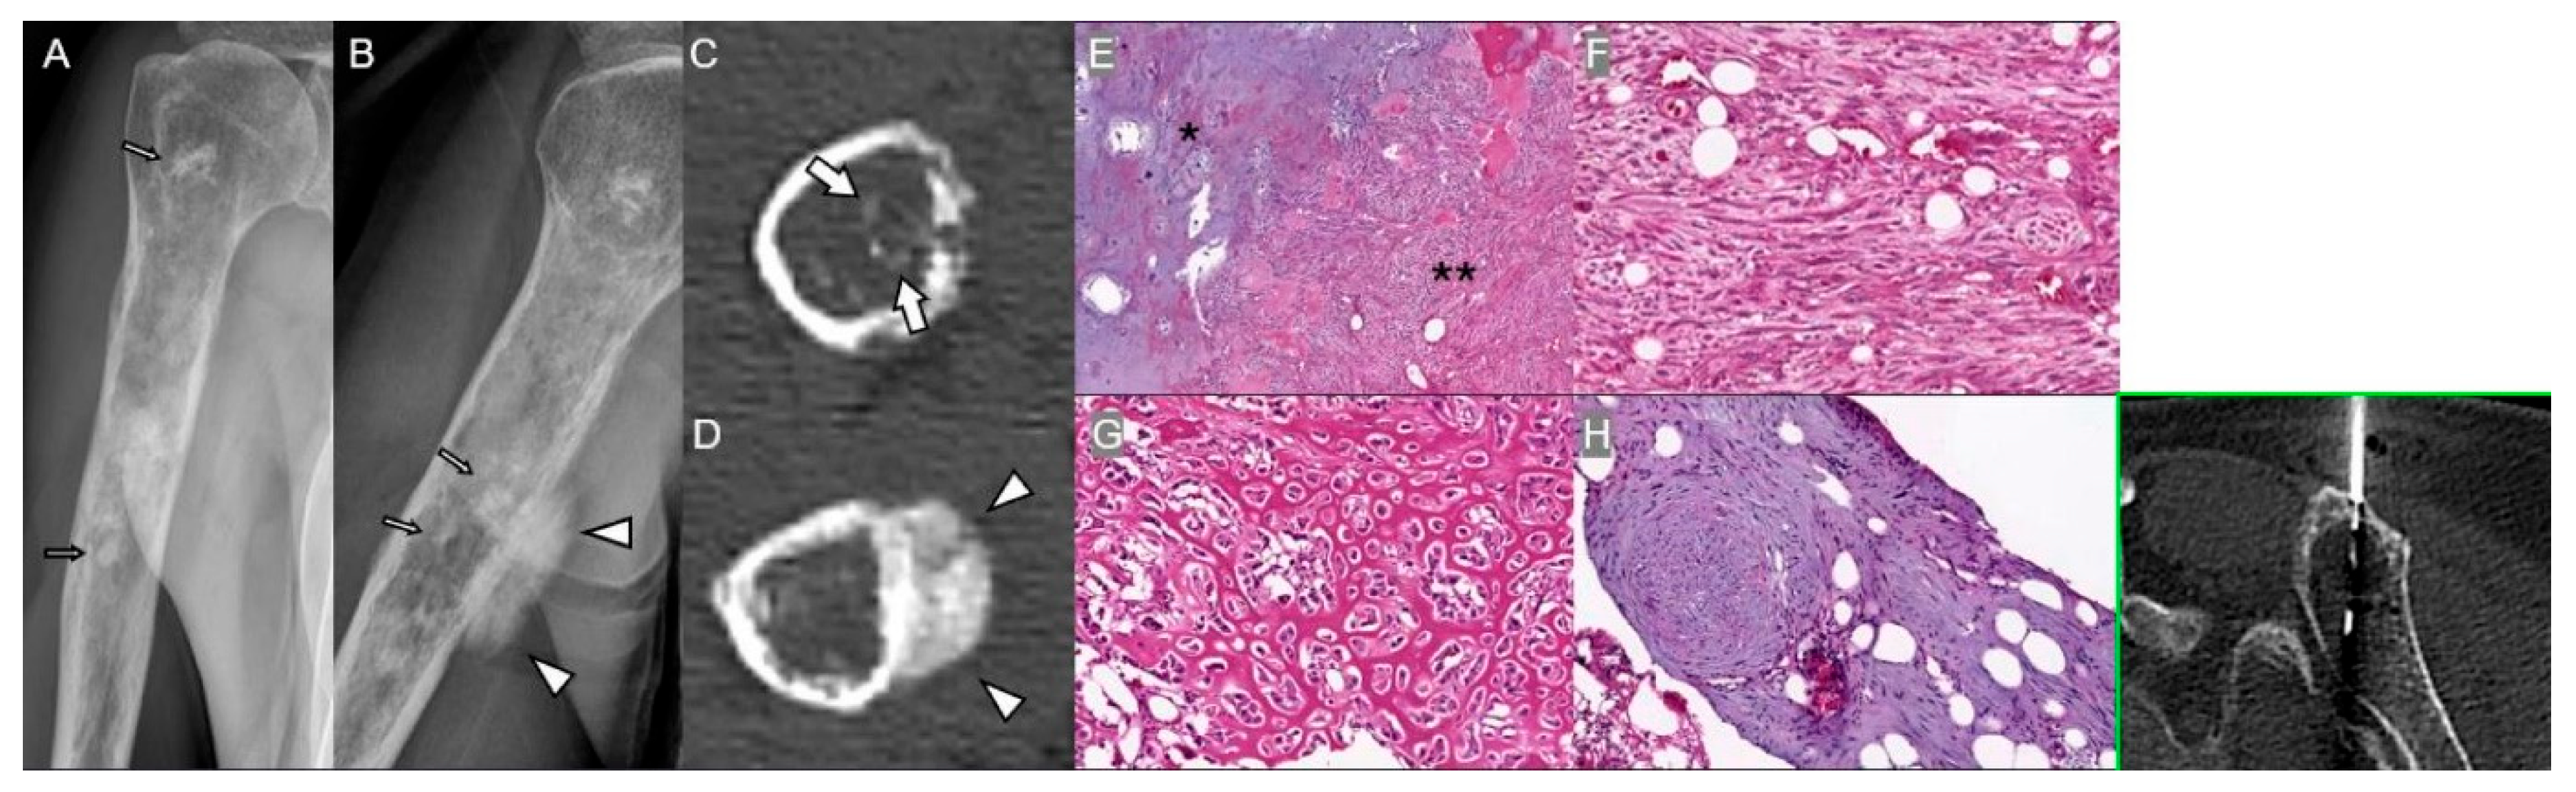

3.3. Bone Infarction